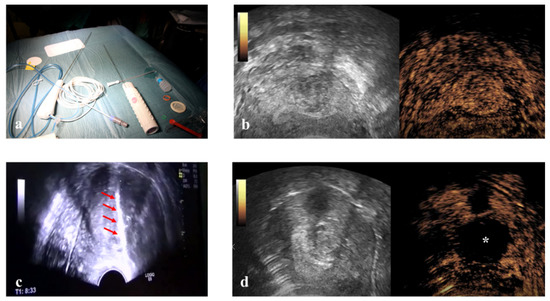

2.4. Therapy

Vaginal ultrasound-guided RFM: unconscious sedation or spinal anesthesia and dorsal position were performed on an outpatient basis after a TV ultrasound re-evaluation of the patient. Before ablation the VT track system (VirtuTRAX, CIVCO Medical Solutions, Coralville, IA, USA) was set and used together with the volume navigation system (V-Nav, LOGIQ E9, GE Healthcare, Milwaukee, WI, USA). This platform has a Global Positioning System (GPS) tracking capability to generate a 3D operating volume around the patient through the connection between three electromagnetic position sensors (2 attached to the US probe and one secured on the shaft of the RF electrode) and the position-sensing unit (Figure 2). The 10 mm active tip was then synchronized with the tracking device by a manual input of the RF electrode length, thus locating the exact position of the RF electrode and projecting its path on the US monitor during the procedure. More specifically, this system is able to guarantee an in-plane approach by displaying a green line on the B-mode when the axis of the electrode fully matches the US scan plane with the projection of the active tip marked as a square, which becomes smaller as the RF electrode approaches the image plane. From that moment onwards, the path of the RF electrode is represented by a dashed line, the prospective RF electrode path is represented by a dotted line and its active tip is located with a green V [21] (Figure 2).

Once the safest path to the target fibroid was identified both via ultrasound (TV or TA) and optically (L-RFMs and H-RFMs), the electrode was appropriately placed into the target fibroid under US real-time guidance and VT [21]. Ablation was performed with the ‘‘moving shot and stepping shot’’ technique [22], whereby the RF electrode was inserted in the distal part of the fibroid and then moved backward in steps of 5–10 s. The RF generator operated at 480 kHz with a maximum power of 200 W and at a temperature ranging from 40 to 99 °C [23]. The chosen working temperature within the fibroids was 85 °C with an automatic adjustment of the power by the device to maintain the selected temperature. Since the RF ablation time depends not only on the temperature but also on the impedance of the tissues, the tip of the electrode was cooled through a system of recirculation of cold saline solution in order to avoid the phenomenon of carbonization. Continuous US was used to monitor the procedure. The total time of ablation was determined based on increased echogenicity and continued until the echo-enhanced area reached 80–90% of the whole fibroid. At the end of ablation CEUS was performed in order to detect any eventual remaining area on enhancement (Figure 2) [21].

Figure 2. (a) Electromagnetic sensors attached to the transvaginal probe and to RF electrode connect to the low-field magnetic generator (cubic box) to provide a 3D operating volume navigation. (b) Virtual needle tracking: the path of the electrode is the dashed line and the hyper-echogenicity of RF ablation is precisely behind the active tip located with a green V. (c) Intra-operative CEUS shows residual areas within the myoma still to be treated. (d) Echo-enhanced area after a complete RF ablation of a fibroid.